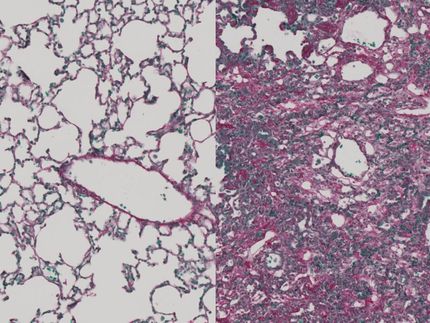

Fibrosis is a perfidious disease. Scar tissue increasingly and irreversibly replaces healthy tissue. The result is that organs such as the lungs, liver or kidneys lose function. In the case of the lungs, more than 80 percent of fibrosis are only detected at a late stage – when the tissue is already extensively scarred and can no longer be saved. Life expectancy for patients with lung fibrosis is then frequently no more than three to five years.

The probe is as nondescript as it is effective: to the naked eye, it appears as a white powder that dissolves in water. When it encounters tissue – e.g. in the form of a biopsy – or bodily fluids in which LOX is active, it begins to fluoresce in a blue colour. “The crucial factor is that we can not only prove the presence of the enzyme but also that it is actually active,” Antoniazzi emphasises.

His aim is to use this probe to create a kind of early warning system. Because although LOX is also active in healthy tissue, the quantities involved are only very small. When fibrosis sets in, activity rises rapidly. “If we can detect this rise in good time, doctors can intervene at an early juncture – before the tissue is irreparably damaged,” Antoniazzi explains.

This probe, which enables early diagnosis of fibrotic disease, is a new development. Until now, lung fibrosis has usually been diagnosed by a process of elimination. A patient with a persistent cough is initially examined for various diseases. If no other explanation can be found, the only diagnosis left is often fibrosis. “This entire process can easily take two years – time during which the disease could already have been treated,” Antoniazzi says. Even hi-res computer tomography, regarded as the gold standard today, can only detect fibrosis when the tissue structure is already altered – which is too late.